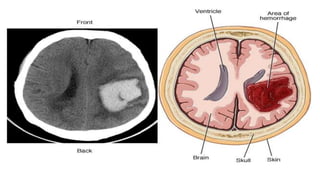

EL was a 34-year-old woman who experienced a 10/10 headache and right lower

extremity paresthesia. She has a history of migraine headaches and other headaches. A

previous MRI scan revealed a left parietal AVM measuring 1 cm × 1.1 cm × 1.3 cm. After

having a baby recently, she saw a neurosurgeon who recommended an angiogram. She

refused the invasive diagnostic test because of the associated risks. Eight months after

the initial diagnosis, EL presented to the emergency department, with headache and right

lower extremity paraesthesia. She was complaining of mild photophobia and nausea. A

CTA was ordered to evaluate her known AVM. The scan revealed a left parietal

intraparenchymal hematoma measuring 1.7 cm × 1.8 cm × 2 cm. The scan also showed

the presence of subarachnoid hemorrhage.

The bleeding pattern and location was consistent with a haemorrhaged AVM. It

was reported to be a Spetzler–Martin grade I AVM; the neurosurgeon decided to

proceed with open surgery to remove the clot and AVM. The patient was

monitored closely in the neurological intensive care unit (NICU) for several days

after her hemorrhage and surgery to ensure continued stability. A second

diagnostic cerebral angiography was performed immediately after the patient’s

open surgery, confirming the complete removal of the lesion. Two months after

surgery, the patient was seen in clinic and had no neurological deficits and was

doing well. She was prescribed anticonvulsant medication, which she will continue

taking for another 7 to 8 months. She is expected to continue with an excellent

recovery.